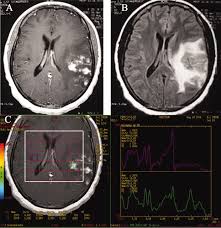

Por ultimo, conoceremos una nueva forma de presentación de schistosoma mansoni, en la que una vez mas el depósito de los huevos en el cerebro, produce múltiples lesiones con la apariencia de pseudotumores.

Forma pseudotumoral difusa de esquistosoma cerebral: una nueva forma de presentación.

Schistosoma mansoni: esquistosomiasis cerebral. Resonancia magnética cerebral muestra una lesión heterogénea mejora con edema circundante.

Se describen dos casos de esquistosomiasis mansoni cerebral con lesiones múltiples pseudotumorales diagnosticado por biopsia cerebral estereotáxica. Ambas pacientes presentaron convulsiones y una con  deterioro visual izquierdo. Las pruebas de imagen revelaron múltiples lesiones cerebrales del parénquima cerebral, pons, el cerebelo y el tálamo. Muestras histológicas del cerebro de los pacientes presentaron múltiples granulomas esquistosomiasis en fases evolutivas diferentes. Todos los pacientes presentaron buena respuesta clínica para el tratamiento y la reversión de las lesiones cerebrales. Esta nueva forma de neuroesquistosomiasis debe estar considerado por los que trabajan en el área endémica de Schistosoma mansoni.

Discusión

Esquistosomiasis cerebral es una afección poco común que se caracteriza por el depósito anómalo de huevos de schistosoma mansoni en el SNC. Los gusanos y los huevos llegan al cerebro por el sistema arterial o venosa retrógrada a través de la sangre (Plexo vertebral de Batson). Los huevos de schistosoma  mansoni y los gusanos en el cerebro provocan una respuesta inmunológica proteica y causan daño vascular.